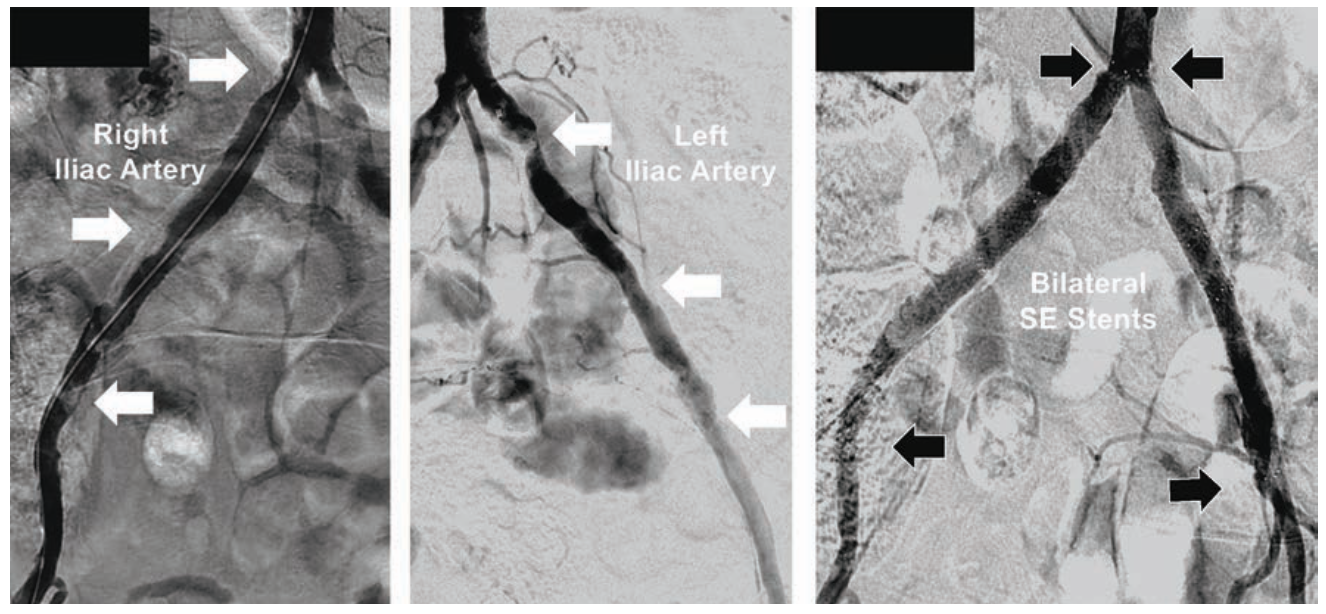

Case #3

A 78-year-old short and obese Hispanic female (4 feet 10 inches, 147 centimeters in height, weight 200 pounds/90.7 kg) was referred with severe bilateral leg claudication, with critical limb ischemia due to a non-healing left foot wound. Using 5 Fr right TRA, abdominal aortography identified a right common iliac stenosis (Figure 3A). A 150 cm TrailBlazer catheter was advanced over a 300 cm Wholey guidewire into both common femoral arteries, and angiography revealed a short chronic total occlusion (CTO) of the left SFA, significant right SFA disease (Figure 3B), with 2-vessel tibial runoff into intact pedal arches bilaterally. The TrailBlazer catheter was further advanced over the Wholey guidewire to a level just above each SFA lesion, to confirm that the distance from right TRA to target lesions did not exceed 150 cm, the length of the device technology catheters being considered for therapy. In the right leg, following injection of 500 mcg of nitroglycerin through the TrailBlazer catheter, a significant 60 mmHg trans-stenotic pressure gradient was measured across the right iliac artery stenosis.

Using the Wholey guidewire, a 90 cm 5 Fr Flexor Shuttle sheath was first advanced into the left external iliac artery. The TrailBlazer catheter was positioned immediately above the left SFA CTO, and connected to a manifold using a Tuohy-Borst adapter (Cook Medical). This allowed injections of 2-4 cc of contrast for facilitating chronic total occlusion (CTO) crossing with a .014-inch 300 cm long Grand Slam (Abbott Vascular) coronary guidewire. Treatment was performed with an .018-inch Armada PTA balloon 6 mm x 60 mm on a 150 cm catheter (Abbott). A 5 Fr-compatible .035-inch EverFlex with Entrust delivery system self-expanding (SE) 7 mm x 80 mm stent on a 150 cm catheter (Medtronic) was deployed in the left SFA, then post-dilated with the Armada 6 mm x 60 mm balloon (Figure 3B). The Flexor Shuttle sheath was redirected using the Wholey guidewire into the right external iliac artery, with exchange for the .014-inch 300 cm guidewire. The right SFA was treated with overlapping EverFlex Entrust SE stents measuring 6 mm x 60 mm and 6 mm x 40 mm, with post-dilatation using an Armada 5 mm x 60 mm balloon (Figure 3B). Pre-dilation of the right common iliac artery stenosis was performed with a .014-inch Viatrac 14 Plus RX 7 mm x 15 mm PTA balloon (Abbott), followed by a .014-inch Herculink Elite RX 7 mm x 18 mm balloon-expandable (BE) stent (Abbott), both on 135 cm monorail catheters (Figure 3A). The patient was discharged 3 hours later following use of a TR Band. Her left foot wound healed within one month, her claudication resolved, and ABIs remained normal at two-year follow-up.

Tips and Tricks for 5 Fr Stenting in the SFA and Iliac Artery

This case predated the availability of the 018 IN.PACT DCB on a 200-cm long catheter. The 150 cm Trailblazer catheter has three marker bands embedded in the distal end, spaced apart by 50 mm. This catheter was used to measure the “intravascular distance” from the hub of the radial access sheath to the SFA target lesions, and verified that PTA balloons and the EverFlex Entrust SE stents on 150 cm catheters could reach the SFA disease. By using a Tuohy-Borst adapter, the TrailBlazer support catheter was converted to a “mini guide” catheter, allowing contrast injections of 2-4 cc to facilitate crossing the left SFA CTO and right SFA disease with an .014-inch guidewire. The Viatrac 14 RX PTA balloon and the Herculink Elite RX BE stent allowed single operator guidewire control for catheter advancement and retrieval from the common iliac artery. The Viatrac and Herculink RX device technologies are both currently available in up to 7 mm diameters for 5 Fr sheath size. At present, treatment with PTA and BE stents in 8 mm diameters or greater requires exchange for a 6 Fr radial access sheath to accommodate the larger diameter over-the-wire catheters.

Case #4

A 72-year-old Asian female (5 feet, 152 cm in height) with debilitating left greater than right buttock and thigh claudication was found to have resting ABIs falling with exercise from 0.80 down to 0.65 in the right leg, and 0.68 down to 0.40 in the left leg. Diagnostic angiography using 5 Fr right TRA demonstrated severe bilateral common and external iliac artery disease, and internal iliac artery occlusions (Figure 4), with no significant infrainguinal vascular disease. A 300 cm Wholey guidewire was used to direct a 110 cm 5 Fr Flexor Shuttle sheath into the distal abdominal aorta, with advancement of a 300 cm coronary guidewire across each iliac artery. Pre-dilatation was performed in both iliacs using a Viatrac 14 Plus RX 7 mm x 15 mm PTA balloon. Subsequently, two overlapping EverFlex Entrust 8 mm x 80 mm SE stents were deployed in each iliac artery to treat the diffuse disease. Post deployment was performed with the Viatrac 14 Plus RX balloon. The patient was discharged 3 hours later following use of a TR Band.

Tips and Tricks for 5 Fr Bilateral Iliac Artery Stenting

5 Fr TRA for iliac artery stenting can be accomplished in most women with peripheral Herculink Elite RX BE stents up to 7 mm in diameter and 18 mm in length, and EverFlex Entrust SE stents up to 8 mm in diameter and 150 mm in length. Primary therapy for bilateral aortoiliac ostial disease in women with small radial arteries can be performed using bilateral radial access and .014-inch guidewires. Advancement of two 5 Fr Sublime 120 cm guide sheaths into the terminal abdominal aorta will facilitate pre-dilatation with “kissing balloons” using two Viatrac 14 plus RX PTA balloons, followed by two Herculink Elite RX BE “kissing stents” up to 7 mm in diameter. Endovascular therapy for short iliac artery CTOs has been accomplished using 5 Fr TRA. However, most operators may prefer 6 Fr or 7 Fr femoral artery access for treating women with iliac CTOs, so that the rare complication of iliac artery perforation can be immediately treated using stent-graft implantation with a Viabahn endoprosthesis (Gore). Lower profile .018-inch Viabahn delivery catheters currently require 6 Fr for 6 mm devices, and 7 Fr for 7 mm and 8 mm devices, and are available only in 120 cm catheter lengths.